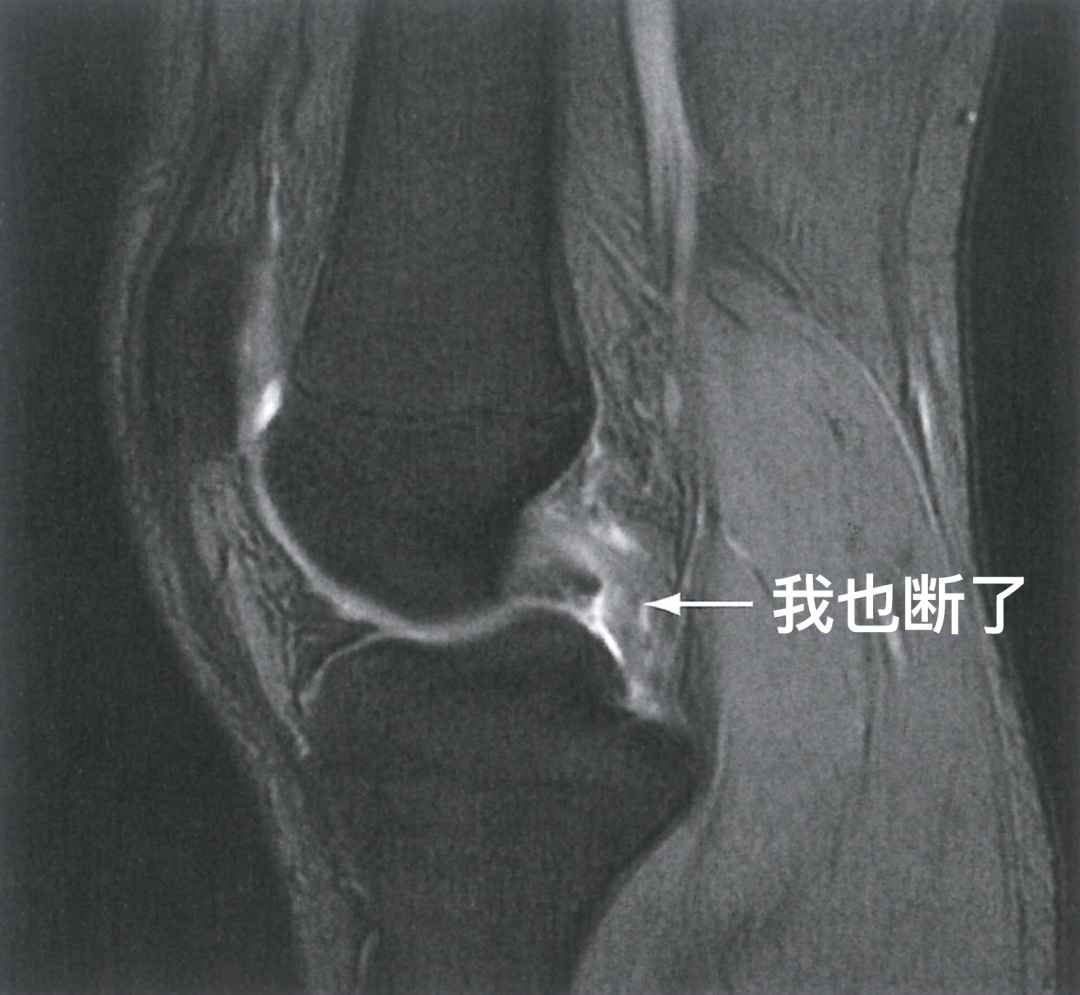

图 5 后交叉韧带撕裂

前交叉韧带能断,后交叉韧带一样也有可能被扯断。比如一不小心跌倒,膝盖没跪碎,但却有可能把后交叉韧带给跪断。骑着电瓶车在马路上摔倒,一下子膝盖敲到了地上,不少叔叔阿姨的韧带就是这样断了。类似的损伤同样可以通过膝关节MRI来诊断。这不,一做就发现,后交叉韧带真的会断!